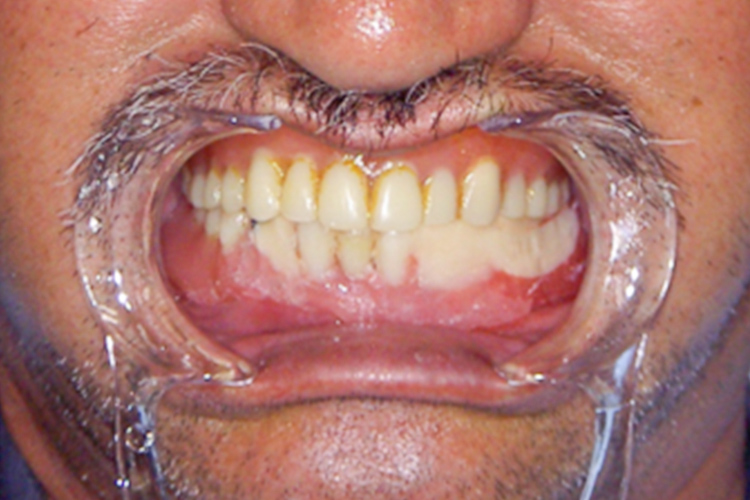

治療前

治療後